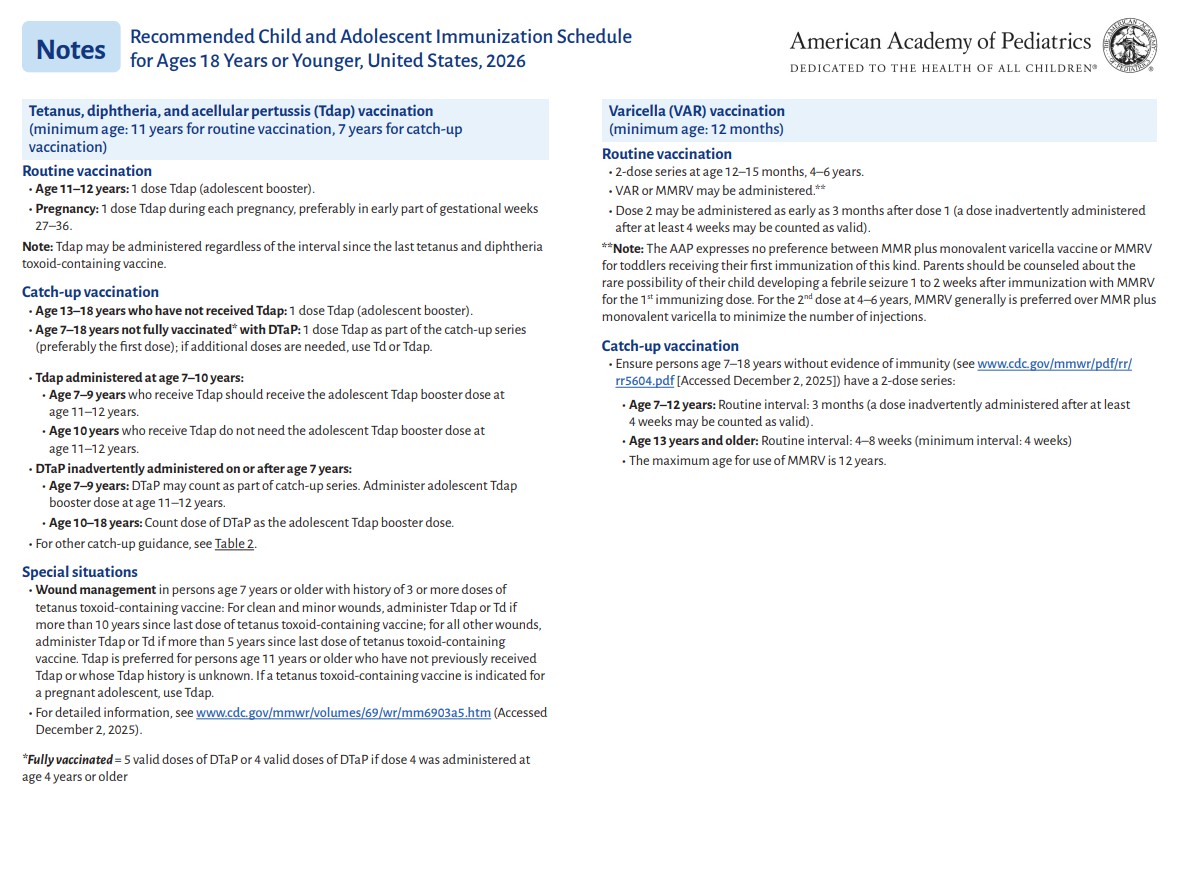

p 3

p 4